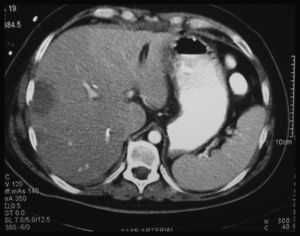

A los 15 días, estando con la fístula biliar, presenta una hemobilia masiva más un hemoperitoneo con importante repercusión hemodinámica y descenso del hematocrito a 18%, precisando transfusión de 6 UI de sangre. Fue necesario realizar cirugía urgente evidenciando hemorragia procedente de una rotura de la AHD, próxima a la inserción del clip de la arteria cística, reparándose con microcirugía. A las 48 h, el paciente desarrolla un FHF con insuficiencia renal, respiratoria y hemodinámica y la actividad de protrombina cae al 20%, a pesar de la administración de plasma. La TC abdominal muestra una isquemia con signos de necrosis del LHD extendida al S. IV (fig. 2). Se intenta realizar una hepatectomía derecha ampliada pero resulta imposible debido a la gran inestabilidad hemodinámica, por lo que se indica TH urgente, que se realiza a las 48 h desde la inclusión (con técnica de piggy-back, y la vía biliar se reconstruye con una nueva HY-Roux). A la semana postrasplante presenta una fístula biliar de alto débito, siendo reintervenido y encontrando una dehiscencia completa de la HY-Roux y, debido a la mala situación del asa yeyunal y del espacio inframesocólico por peritonitis previa, se decide exteriorizar la bilis mediante una sonda colocada en la vía biliar del hígado donante. Al 20 día post-TH fue reintervenido realizando una coledococoledocotomía terminoterminal, colocando un drenaje nasobiliar como tutor.

Existen 3 casos descritos en la literatura médica de TH secundario a lesión exclusiva de la AHD, y solo uno de ellos por FHF. Bacha et al.34 publican un caso de necrosis del LHD, tratado inicialmente con drenajes percutáneos de colecciones intrahepáticas, y que a los 3 meses requirió una trisegmentectomía derecha presentado un FHF tras la cirugía y necesitó un TH. En nuestro paciente, el FHF se desarrolló por la rotura de un pseudoaneurisma de la AHD, a las 2 semanas de la reparación biliar, probablemente relacionado con la lesión de la pared arterial durante la colecistectomía quedando así debilitada. La presencia de una fístula biliar tras la primera reparación también pudo contribuir a la rotura arterial ya que se han descrito lesiones vasculares en pacientes con fístula biliar y/o pancreática. Al FHF pudo contribuir la existencia de un hígado patológico (2 intervenciones consecutivas, una peritonitis biliar reciente y la presencia de una fístula biliar externa) y de necrosis que afectó a todo el LHD extendiéndose al S. IV (fig. 2), con un lóbulo izquierdo pequeño. Los otros 2 pacientes con lesión de la AHD fueron trasplantados por CBS15,32.